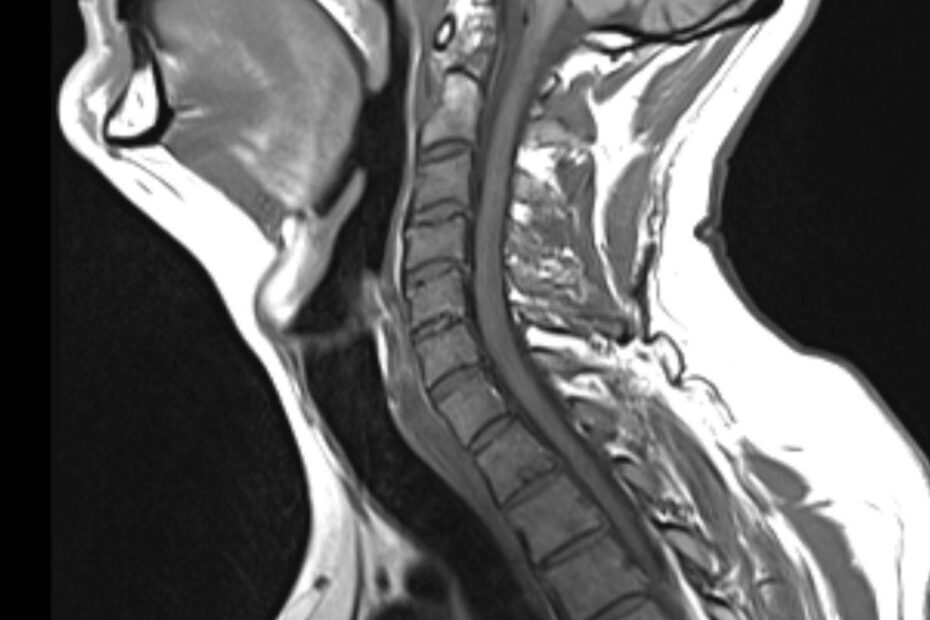

Die Magnetresonanztomographie der Halbwirbelsäule, kurz MRT HWS genannt, ist ein bildgebendes Diagnoseverfahren. In einer MRT HWS ist es möglich, den Bereich der Halswirbelsäule mit allen anatomischen Strukturen bildlich darzustellen. Besonders im Falle eines Verdachts auf Bandscheibenvorfall im Bereich der HWS ist eine Magnetresonanztomographie die bevorzugte Diagnosemethode. Jährlich erleiden 180.000 Personen einen Bandscheibenvorfall. Dieser kann sich … MRT HWS (Halswirbelsäule) weiterlesen